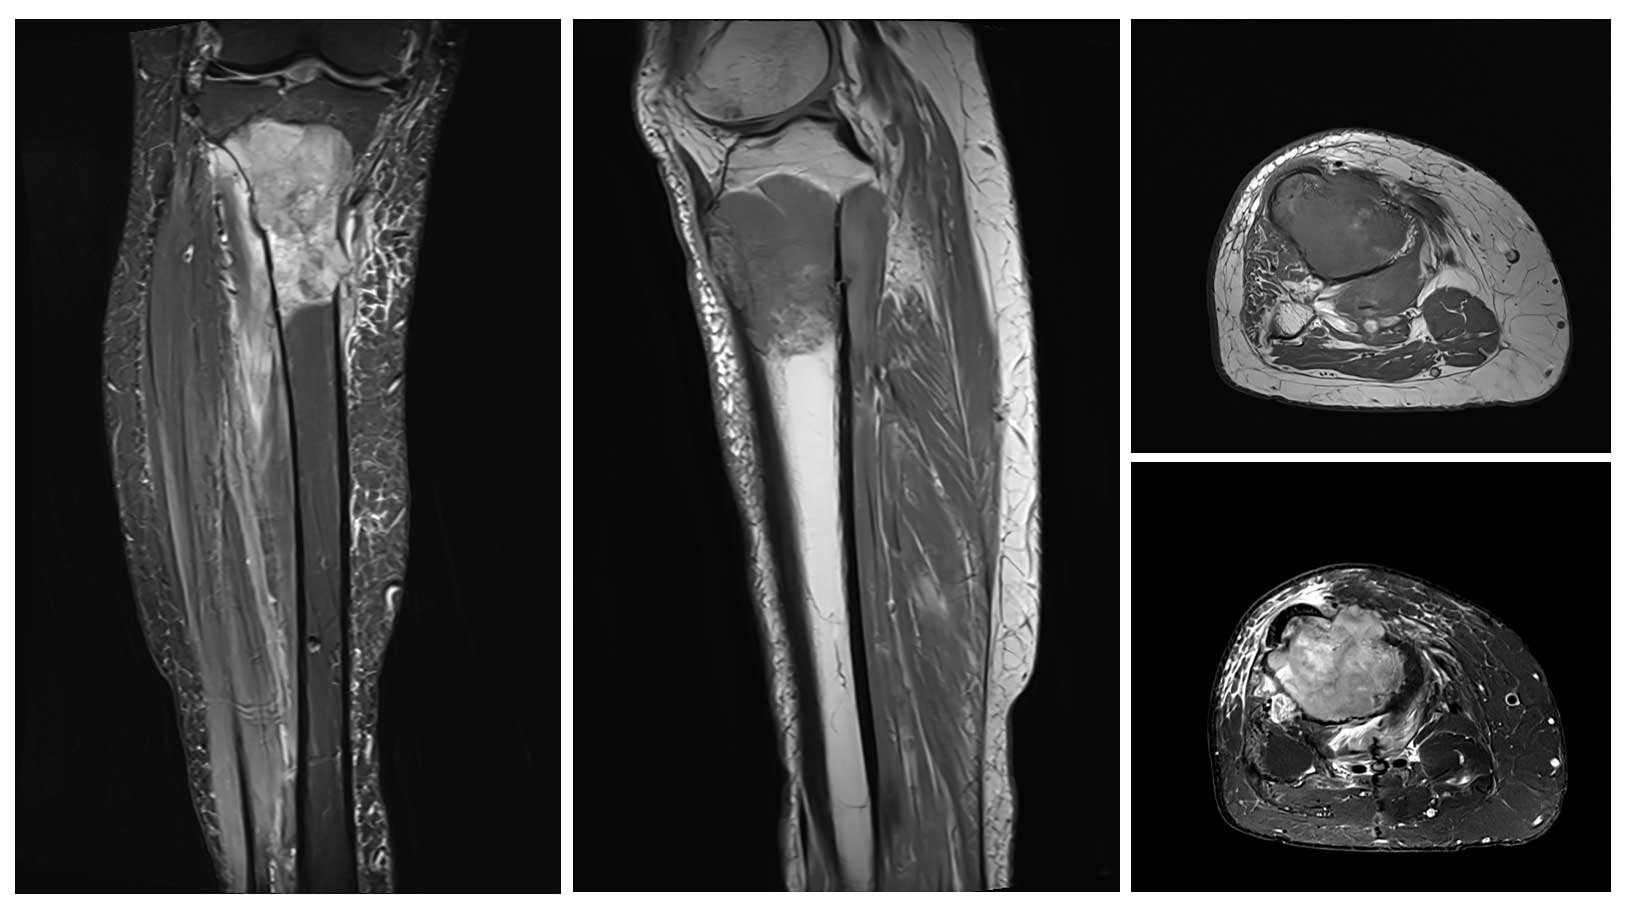

70 yaş erkek hasta, sağ diz çevresinde ağrı ve şişlik şikayetiyle başvurdu. Yapılan radyolojik incelemeler ve biyopsi sonucunda proksimal tibia osteosarkomu tanısı konuldu.

Ameliyat Öncesi: MR’da aynı lokalizasyonda kemiğin dışına taşmış ve çevresel yaygın ödeme neden olmuş tümör dokusu görülmekte.